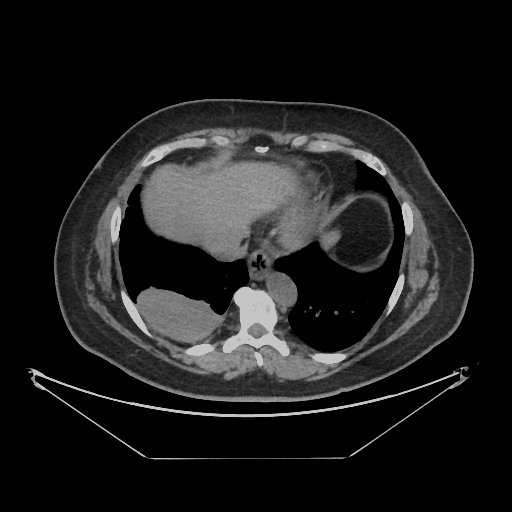

Original VENOUS CT scan

No window - Raw intensity values

Lung window (WL -600, WW 1500 β†’ Low βˆ’1350, High +150)

Mediastinum window (WL 40, WW 400 β†’ Low βˆ’160, High +240)